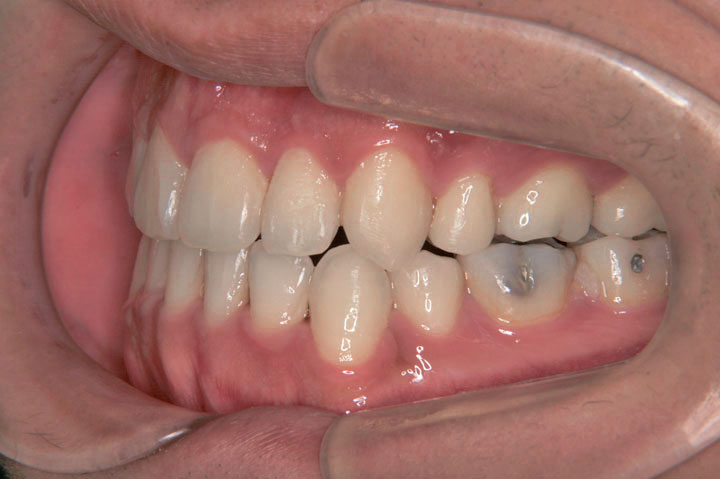

臼歯部不正(交叉咬合など)

叢生(乱ぐい歯)

下顎前突(受け口)

歯並びのガタガタと顎のズレを気にして来院された成人の患者さんです。本来であれば、外科矯正の適応とご説明いたしましたが、ご本人様もそこまでは希望されないとのことで、通常のエッジワイ治療として、デーモンシステムによる治療を行っております。治療期間は2年5ヶ月でしたが、非外科系の矯正治療としては、非常に良好な結果と考えております。